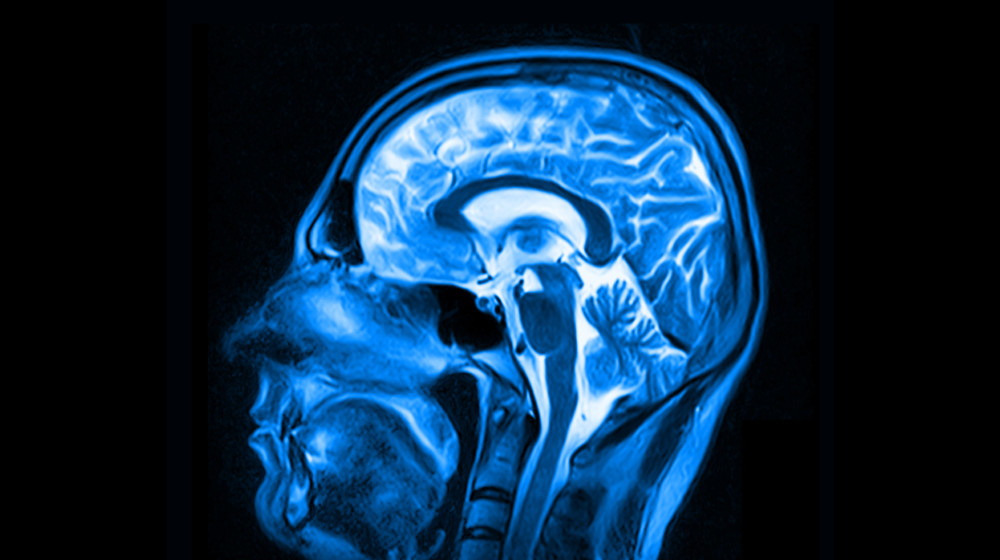

• МРТ с диффузионно-взвешенной визуализацией